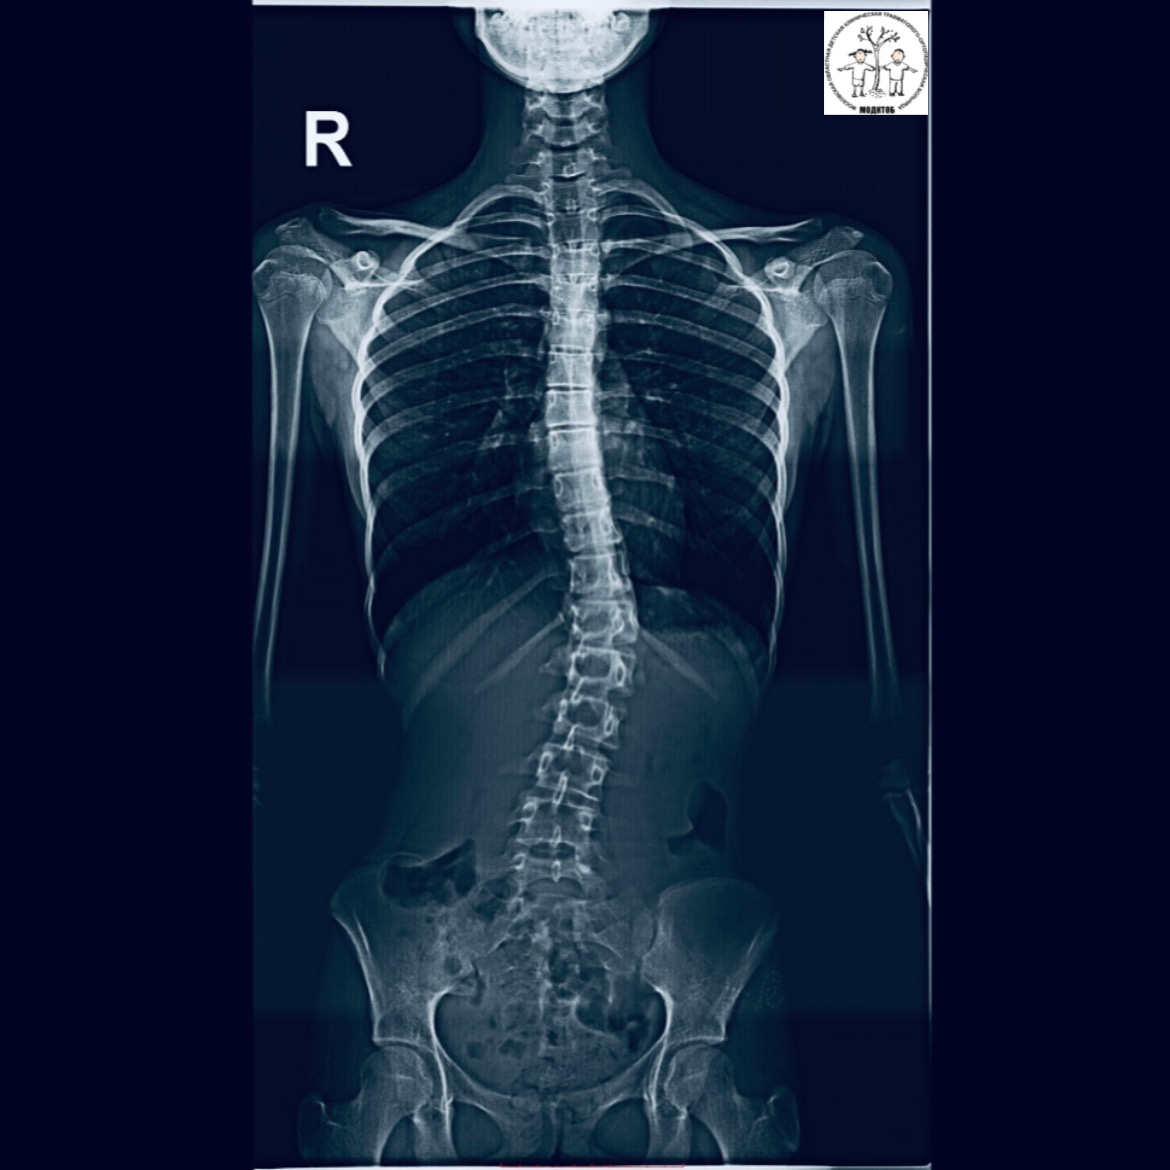

🔹Панорамная рентгенография — это современный метод диагностики, который обеспечивает высокую точность и скорость получения снимков, что позволяет нашим врачам ставить точные диагнозы и назначать оптимальное лечение. Цифровая рентген-сшивка имеет множество преимуществ: ✔️ высокое качество изображения, четкие и детализированные снимки; ✔️ минимальная доза облучения; ✔️высококвалифицированная диагностика костно-суставной системы у детей с травмами и различными патологиями опорно-двигательного аппарата различной этиологии. 💬 «Отделение лучевой диагностики МОДКТОБ – уникальное отделение, сотрудники которого работают в тесном сотрудничестве со всеми структурными подразделениями больницы. Сегодня невозможно представить травматологию и ортопедию без современных методов лучевой диагностики и цифрового анализа. С уверенностью могу сказать, что установленный аппарат ZEXIRA DREX-ZX80 CANON с функцией сшивки рентгенологических изображений — один из немногих в Московской области, имеющий данную в

🔹Панорамная рентгенография — это современный метод диагностики, который обеспечивает высокую точность и скорость получения снимков, что позволяет нашим врачам ставить точные диагнозы и назначать оптимальное лечение.

Цифровая рентген-сшивка имеет множество преимуществ:

✔️ высокое качество изображения, четкие и детализированные снимки;

✔️ минимальная доза облучения;

✔️высококвалифицированная диагностика костно-суставной системы у детей с травмами и различными патологиями опорно-двигательного аппарата различной этиологии.

💬 «Отделение лучевой диагностики МОДКТОБ – уникальное отделение, сотрудники которого работают в тесном сотрудничестве со всеми структурными подразделениями больницы. Сегодня невозможно представить травматологию и ортопедию без современных методов лучевой диагностики и цифрового анализа. С уверенностью могу сказать, что установленный аппарат ZEXIRA DREX-ZX80 CANON с функцией сшивки рентгенологических изображений — один из немногих в Московской области, имеющий данную возможностью выполнения», — прокомментировал заведующий отделением лучевой диагностики МОДКТОБ Фомченко Антон Александрович.